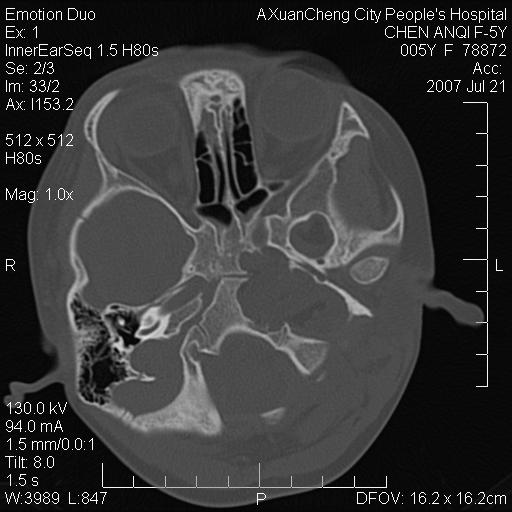

标题: PED0273:5岁,左耳流脓痛疼一周,颅底骨质破坏 [打印本页]

标题: PED0273:5岁,左耳流脓痛疼一周,颅底骨质破坏

患儿5岁,左耳流脓痛疼一周,左外耳道肉芽组织填塞 软组织窗显示病灶内结节状低密度影为气体密度

左侧中耳炎并胆脂瘤,左颞骨岩部骨质破坏并颅内感染积气。

考虑化脓性中耳乳突炎伴胆脂肪瘤形成并左颞叶感染,不除外合并嗜酸性肉芽肿.